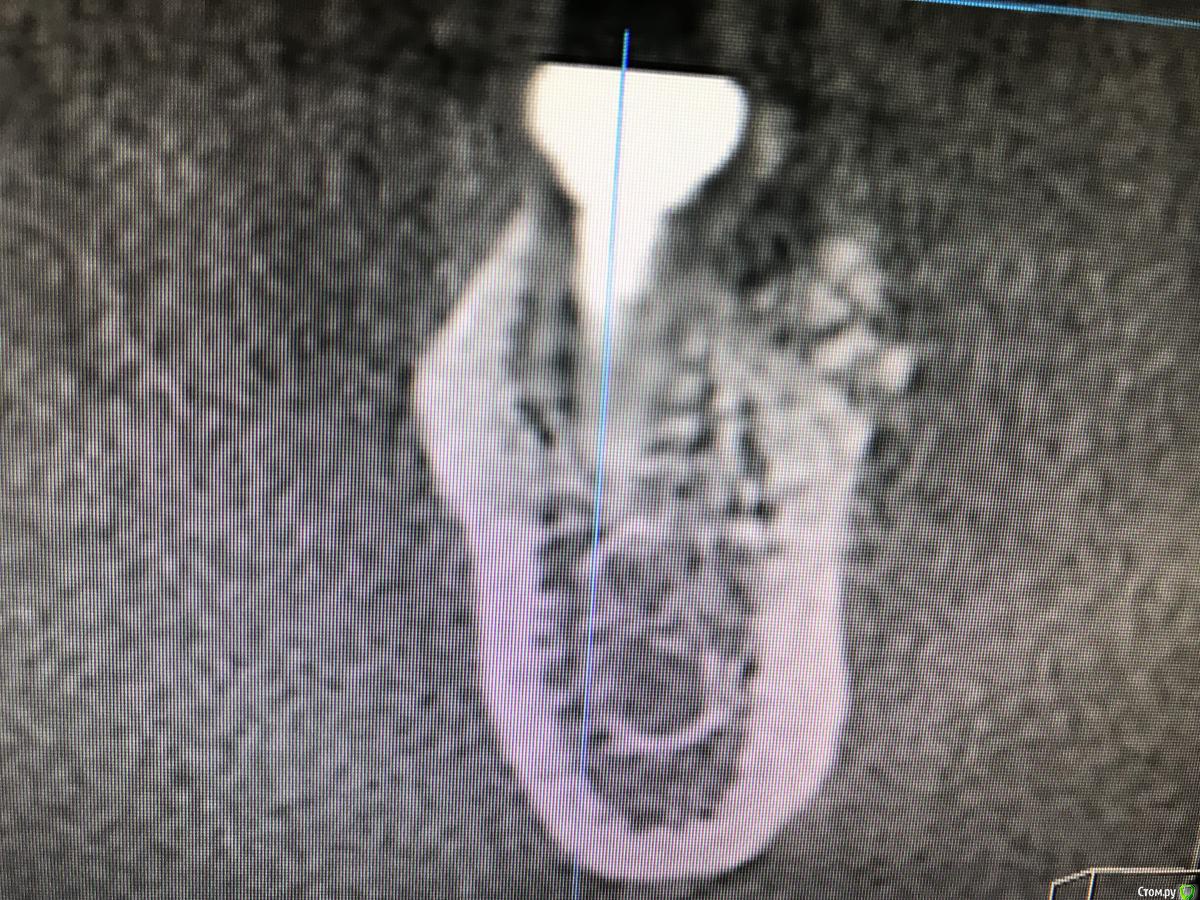

колесников Опубликовано 15 марта, 2019 Автор Поделиться Опубликовано 15 марта, 2019 Вот так выглядит интегрированый графт и соответственно не созревший. Время ожидания примерно равнозначное Ссылка на комментарий

Bier Опубликовано 15 марта, 2019 Поделиться Опубликовано 15 марта, 2019 а на каком уровне срез? Ссылка на комментарий

колесников Опубликовано 15 марта, 2019 Автор Поделиться Опубликовано 15 марта, 2019 По середине Ссылка на комментарий

колесников Опубликовано 16 марта, 2019 Автор Поделиться Опубликовано 16 марта, 2019 (изменено) Ну как бы тут все очевидно. Слева стала костью,справа нет. Но должен вам отметить,что даже в случае неудачи (как кажется)потери нет. Задача стояла не увеличить объём для имплантации или укрыть Имплант,а снять напряжение с вершины гребня и дать созреть десне. Имплант в нативной кости,он интегрирован,десна успела созреть за это время,возможно будет не так объёмно как хотелось бы,но у меня в запасе этап раскрытия ,фдм зарос ,есть с чем поработать. Все что не интегрировалось ,лизируется самостоятельно,выскребать ничего не нужно,ещё подождать. Изменено 16 марта, 2019 пользователем колесников Ссылка на комментарий